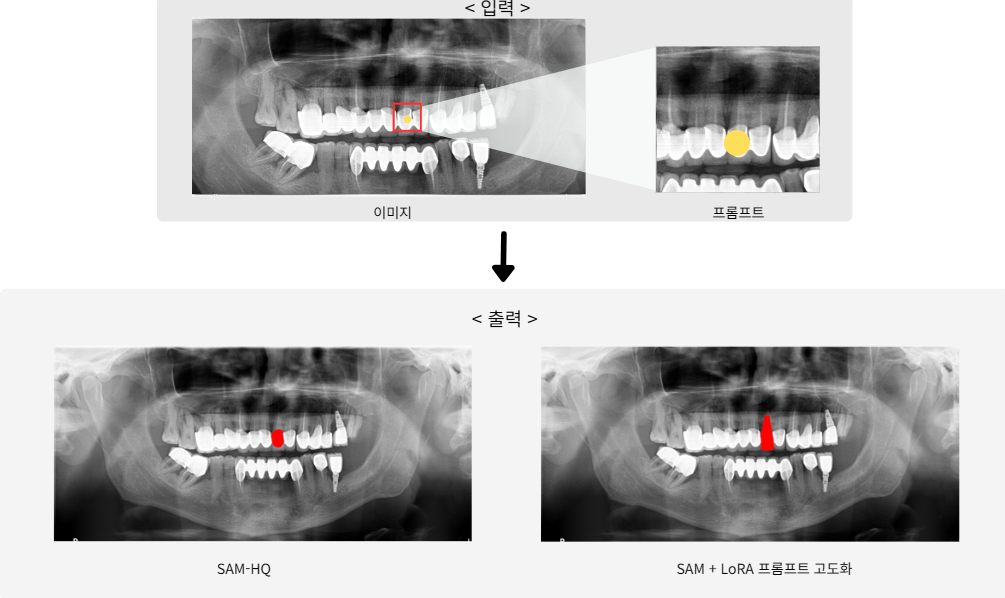

• Prompting: From simple center-point prompts → to iterative correction prompts (up to 11 iterations)

Iterative Prompt Strategy

Iterative prompt refinement for correcting under-/over-segmentation

• SAM-HQ baseline Dice score: 0.748

• SAM-HQ + LoRA + iterative prompts: 0.914

• Decoder-only and HQ-module-only LoRA also improved, but Encoder+Decoder LoRA gave best results

Result Comparison 2

Blurred region segmentation comparison